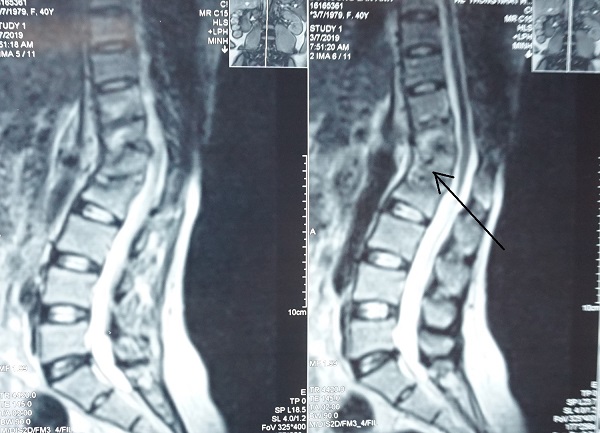

Kết quả chụp MRI tại Bệnh viện Quốc tế City cho thấy, bệnh nhân N.A bị lao cột sống 4 đốt D11-D12, L1-L2, có khối áp xe to dọc cơ thắt lưng chậu trái, được chỉ định phẫu thuật tránh biến chứng.

Lao cột sống 4 đốt D11 D12 – L1 L2.